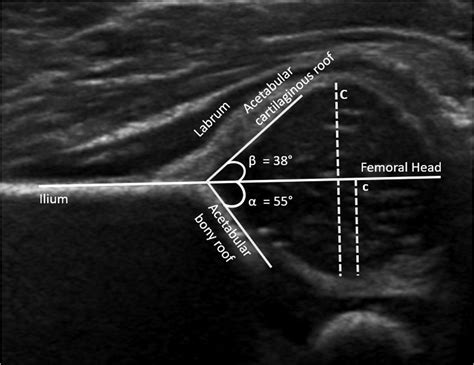

Interpreting the Results of an Infant Hip Ultrasound

The results of an Infant Hip Ultrasound are interpreted by a radiologist or orthopedic specialist who is trained in pediatric imaging. The images are evaluated for several key factors, including:

• The shape and depth of the acetabulum

• The position of the femoral head within the acetabulum

• The presence of any abnormalities or dislocations

• infant hip ultrasound normal angles